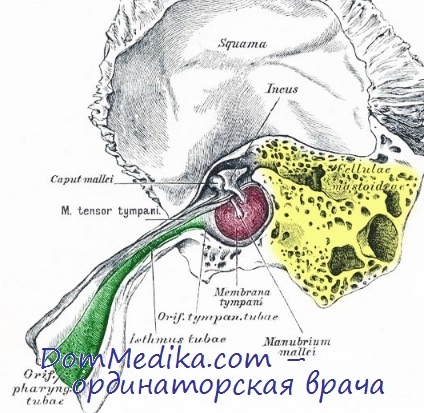

Анатомия сосцевидного отростка